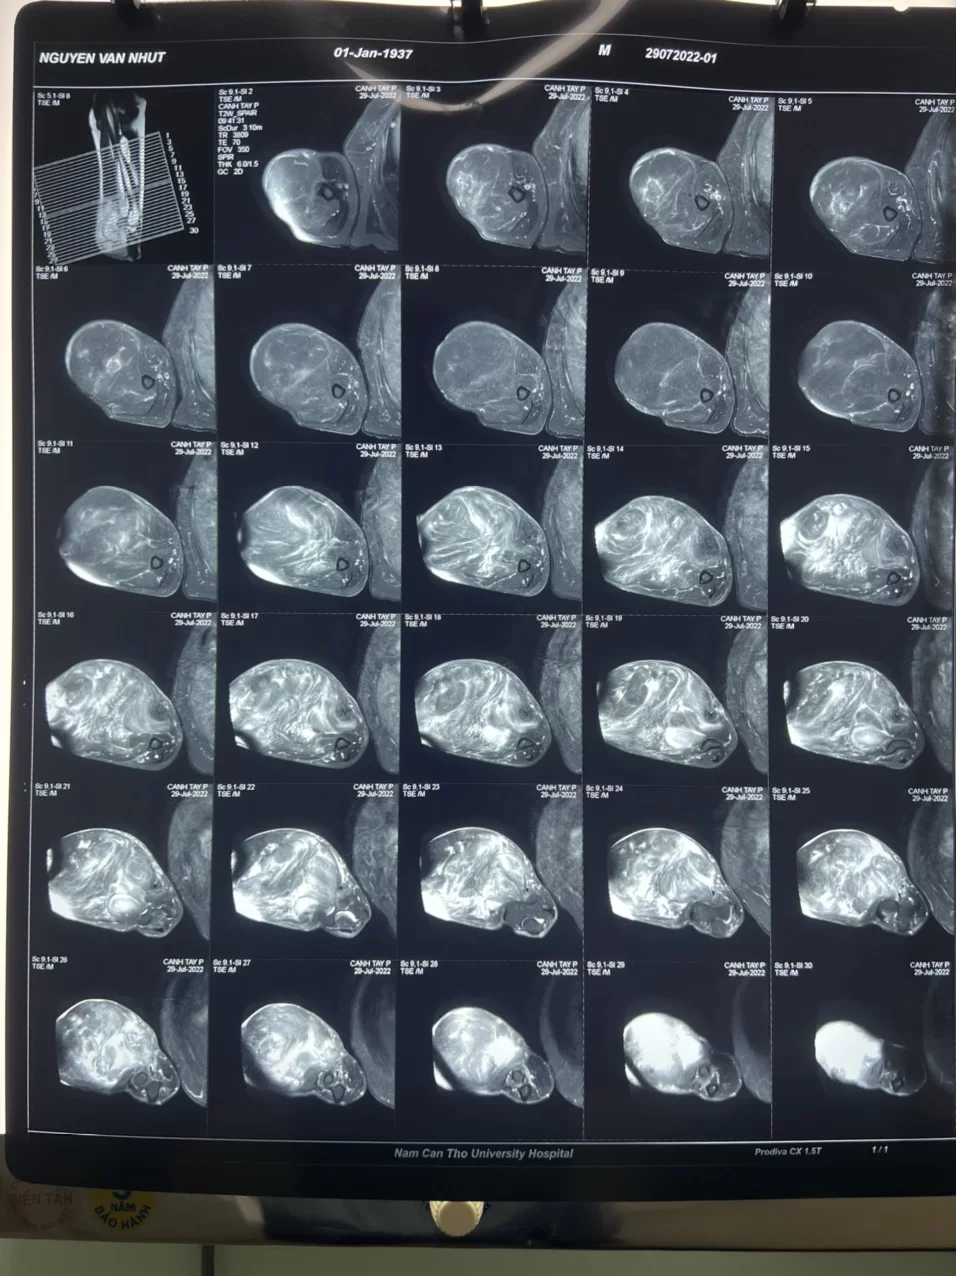

Sau khi được BSCKII. Ngô Nhất Linh, trưởng khoa ung bướu khám đánh giá bác N mang khối bướu 30 cm, tăng sinh mạch máu, có sẹo mổ dài 20 cm, có ổ loét da 2cm dễ chảy máu, di động tốt, bờ đều, chắc chiếm 2/3 dưới ngoài trước cánh tay (P), bệnh nhân kèm tăng huyết áp. Bệnh nhân được đánh giá bướu bằng chụp cộng hưởng từ cánh tay (P) và làm các xét nghiệm đánh giá trước mổ. Bệnh nhân được tập thể y bác sĩ khoa Ung bướu hội chẩn chẩn đoán bướu phần mềm cánh tay (P) nghĩ nhiều lipoma hoặc liposarcoma loét chảy máu/ tăng huyết áp/ lão suy. Qua tư vấn kế hoạch điều trị cho bệnh nhân, người bệnh và gia đình đồng ý lựa chọn can thiệp phẫu thuật.

Hình ảnh bệnh nhân trước phẫu thuật